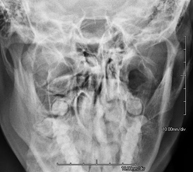

- Neurorradiología

- RX Cráneo

Técnica mediante la cual, utilizando rayos X, se obtienen imágenes del cráneo para su estudio. Indicaciones: traumatismo, cierre precoz de suturas craneales.

- RX Senos Paranasales

Técnica mediante la cual, utilizando rayos X, se obtienen imágenes de los senos paranasales para su estudio. Indicaciones: dificultad respiratoria nasal, tos crónica, cefalea, mucosidad.